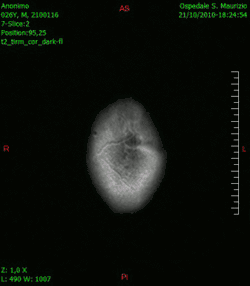

En las imágenes de TC y RM se muestra como una lesión heterogénea, de contorno irregular, que capta contraste en anillo y con un área central necrótica.

Diagnóstico por imagen y glioblastoma

La TC muestra una lesión de morfología irregular, predominantemente hipodensa y fuertemente dishomogénea, debido a la presencia de grandes áreas necróticas de más clara hipodensidad y de áreas sólidas hiperdensas. Estas últimas son la expresión de un rápido crecimiento y por lo tanto de una elevada malignidad. Son frecuentes las zonas hemorrágicas, que van desde pequeños focos a grandes áreas hemáticas que pueden cubrir toda la lesión. Es característica la morfología en "mariposa" si el tumor se asienta en ambos hemisferios a través del cuerpo calloso.

Tras la aplicación de contraste aparecen gruesos anillos alrededor de las áreas necróticas. En la RM, la parte sólida aparece hipointensa en T1 e hiperintensa en T2 con zonas de señal más elevada en las partes de mayor celularidad. Las áreas necróticas, hiperintensas en T2, pueden presentarse hipo-, iso- o hiperintensas en T1 en función del contenido proteico o de productos de la degradación de la hemoglobina. El realce tras el contraste suele ser intenso e irregular en la periferia del tumor e identifica sobre todo la componente celular "proliferativa" de la neoplasia. Son comunes las áreas puntiformes y serpiginosas de ausencia de señal de flujo, asociadas a la presencia de una neovascularización rica. Estos vasos de neoformación patológica carecen de barrera hematoencefálica, lo que explica tanto la abundante impregnación como el edema vasogénico perilesional (véase la sección anterior), debido al paso de líquido al medio extracelular.[72][73]